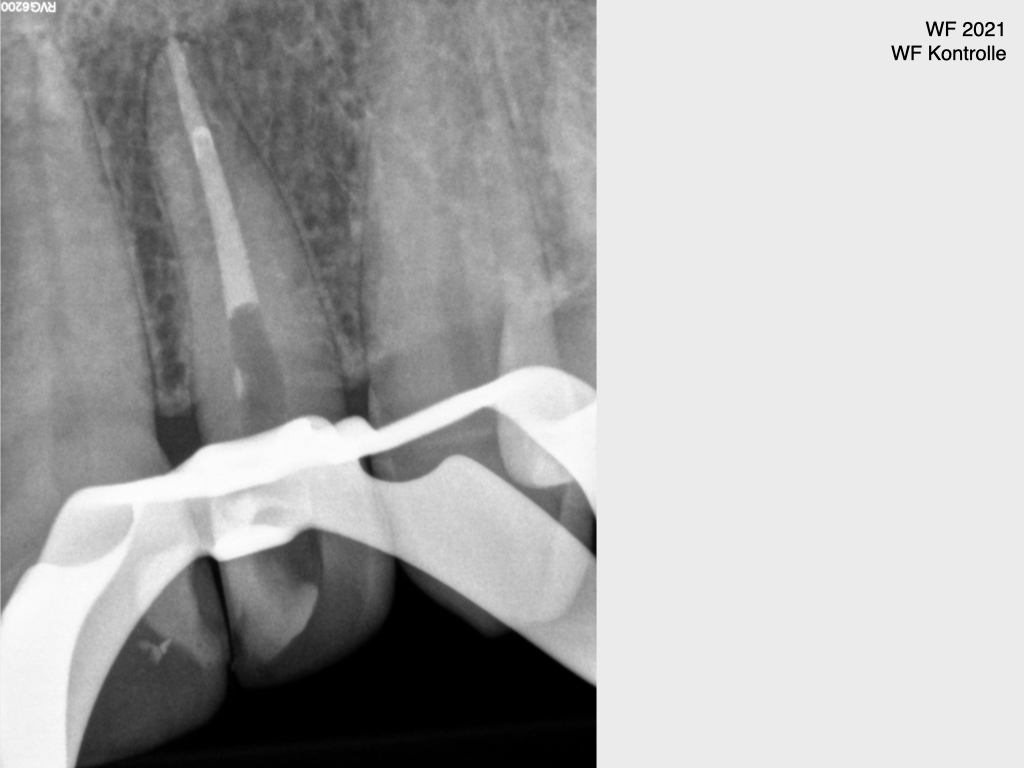

Frontzahn 22 (3)